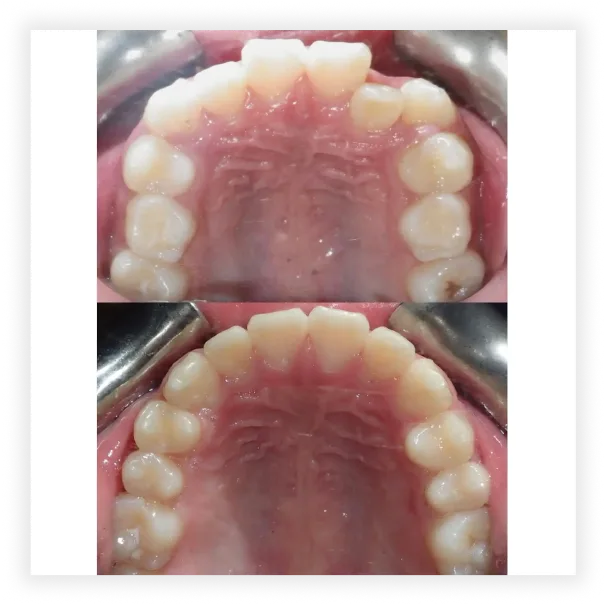

Smile Gallery

Take a look at some of our cases and successful transformations below.

Case #1

Initial Photos

Final Photos